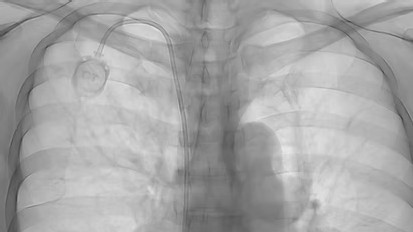

케모포트

중심정맥

중심정맥은 우리 몸에서 심장 가까이에 위치한 굵고 큰 혈관을 말합니다. 이 혈관들은 온몸으로 혈액을 빠르고 넓게 퍼뜨리기 때문에, 약물이나 영양을 효과적으로 전달할 수 있는 중요한 통로입니다.

Central Venous Catheter

중심정맥관 종류

Chemoport